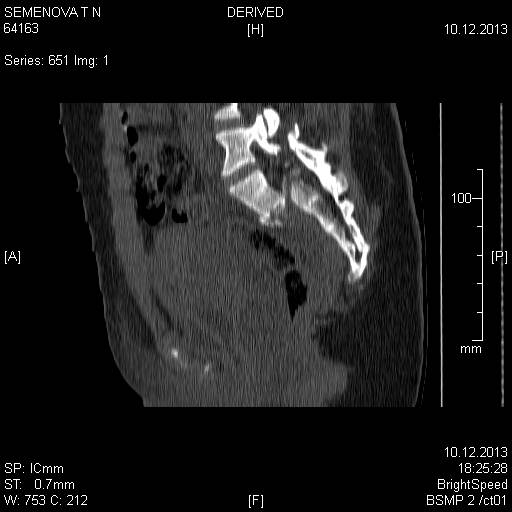

Доброго времени суток коллеги! Прошу вас, подсказать тактику в решении

оперативного лечения следующего сложного повреждения таза. Был ли опыт в

фиксации подобных повреждений?

Травма 03.12.2013,больная переведена из лечебного учреждения соседней

области. На данный момент у больной следующий диагноз: ЗЧМТ,сотрясение

головного мозга;Закр. травма грудной клетки,множественные переломы ребер

справа с повреждением ткани легкого, правосторонний гемопневмоторакс,

состояние после торакоцентеза; Закр.травма живота,разрыв

селезенки,гемоперионеум, состояние после лапаротомиии спленэктомии;

Закр. оскольчатый перелом сред-верх\3 левой бедренной кости, состояние

после накостного металлостеосинтеза; Закр.поперечный переломовывих на

уровне S1S2, многооскольчатый перелом латеральных масс крестца с обеих

сторон,перелом обеих лонных и седалищных костей.

Перелом поперечных отростков L1,L2,L3,L4, L5 позвонка справа. ШОК 3ст.

Вкратце изложил диагноз.